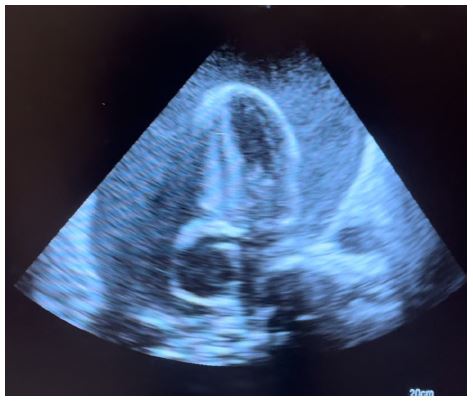

Figure 2: Apical 4 chamber echo view showing massive pericardial effusion with compression of the right side of the heart.

Transthoracic echocardiography is the best diagnostic imaging, useful in diagnosis and management of tuberculous pericardial effusion. Echocardiography can provide an estimate of the size of effusions. Generally, the size of the effusion on echocardiography indicates the volume of pericardial fluid as follows: small (<10 mm), which corresponds to 50-100 mL pericardial fluid; moderate (10-20 mm), corresponding to 100 - 500 mL pericardial fluid and large (>20 mm), corresponding to >500 mL pericardial fluid [19] . The study of Diakité et al. showed 18% of moderate abundance and 81% of high abundance among 49 cases of tuberculous pericarditis [6].